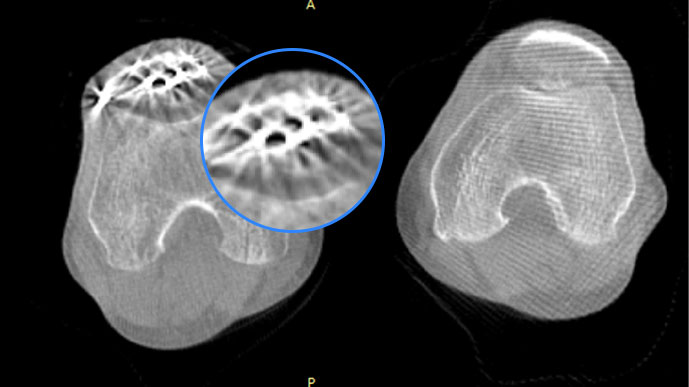

膝关节

关闭金属伪影校正

开启金属伪影校正